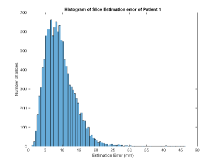

Exp. 1: Segmented adult brain data is used to evaluate our network’s regression performance with known ground truth . 85 brains from the ADNI data set[1] were randomly selected; 70 brains for and 15 brains for . Fig. 2 shows an example slice of the ground truth and the reconstructed .

Here we show for Exp. 1, Exp. 2, and Exp. 3 randomly selected examples of images that have been presented to the network (ground truth) compared to an image sampled at the predicted location.

In these experiments, we present a ground truth (GT) image to the network to estimate the respective transformation parameters needed to reorient the slice in its correct world co-ordinates. Using the transformation parameters, we generated a slice from the 3D atlas in the location where the network has predicted that slice should be (denoted as SVRNet).

The slices are compared side-by-side to give a visual representation of “where the slice really is” and “where the network thinks the slice is”.

0..5.1 Exp. 1:

Slices, extracted from a correctly registered and reconstructed 3D volume, from the testing data set are presented to the network. The predicted slice is extracted from the same volume, using parameters estimated by SVRNet as shown in Fig. 8 and 9.